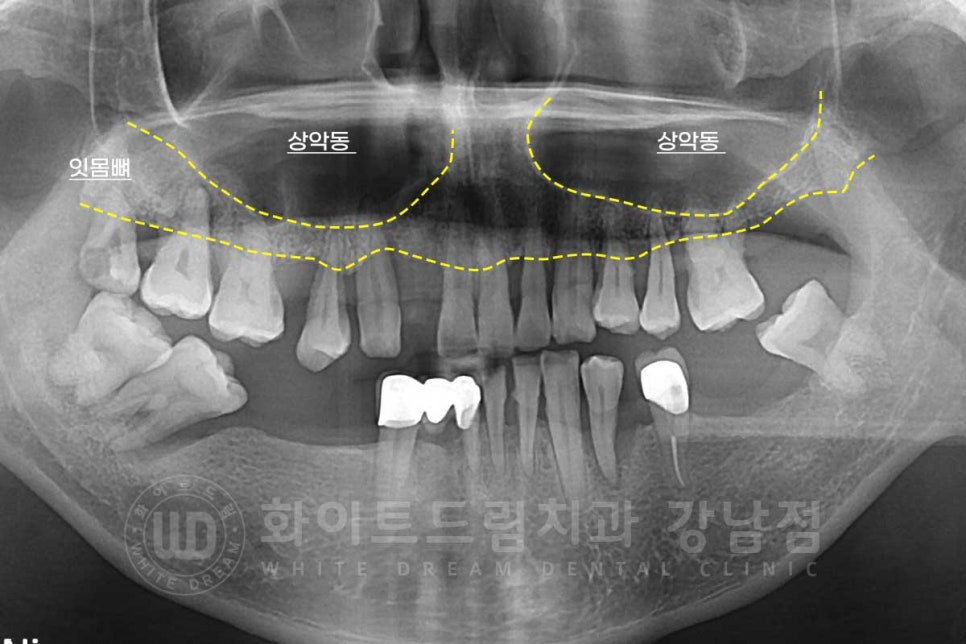

이 중 상악동이 하방으로 많이 내려오는 함기화 현상이 발생한 것이 확인됩니다.

이 때문에 환자분도 잔존 잇몸뼈가 굉장히 얇아진 상태였기에

상악동을 들어 올린 후 뼈이식을 진행하고, 이후 임플란트를 식립하는 과정이 필요했습니다.